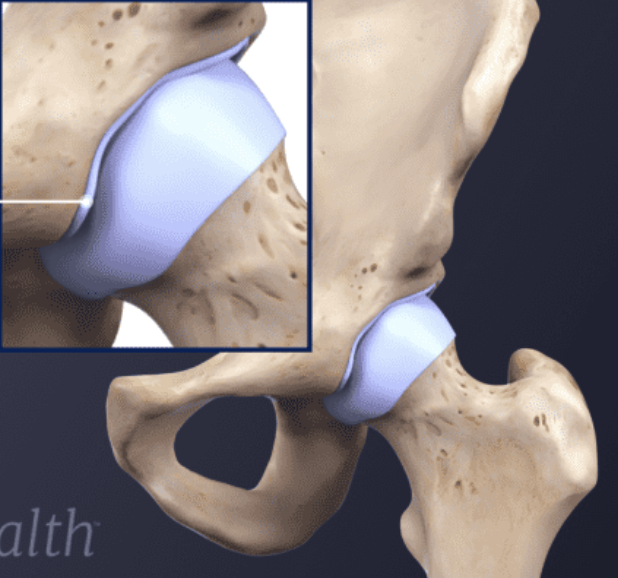

Acetabular labrum

Fibrous joint capsule